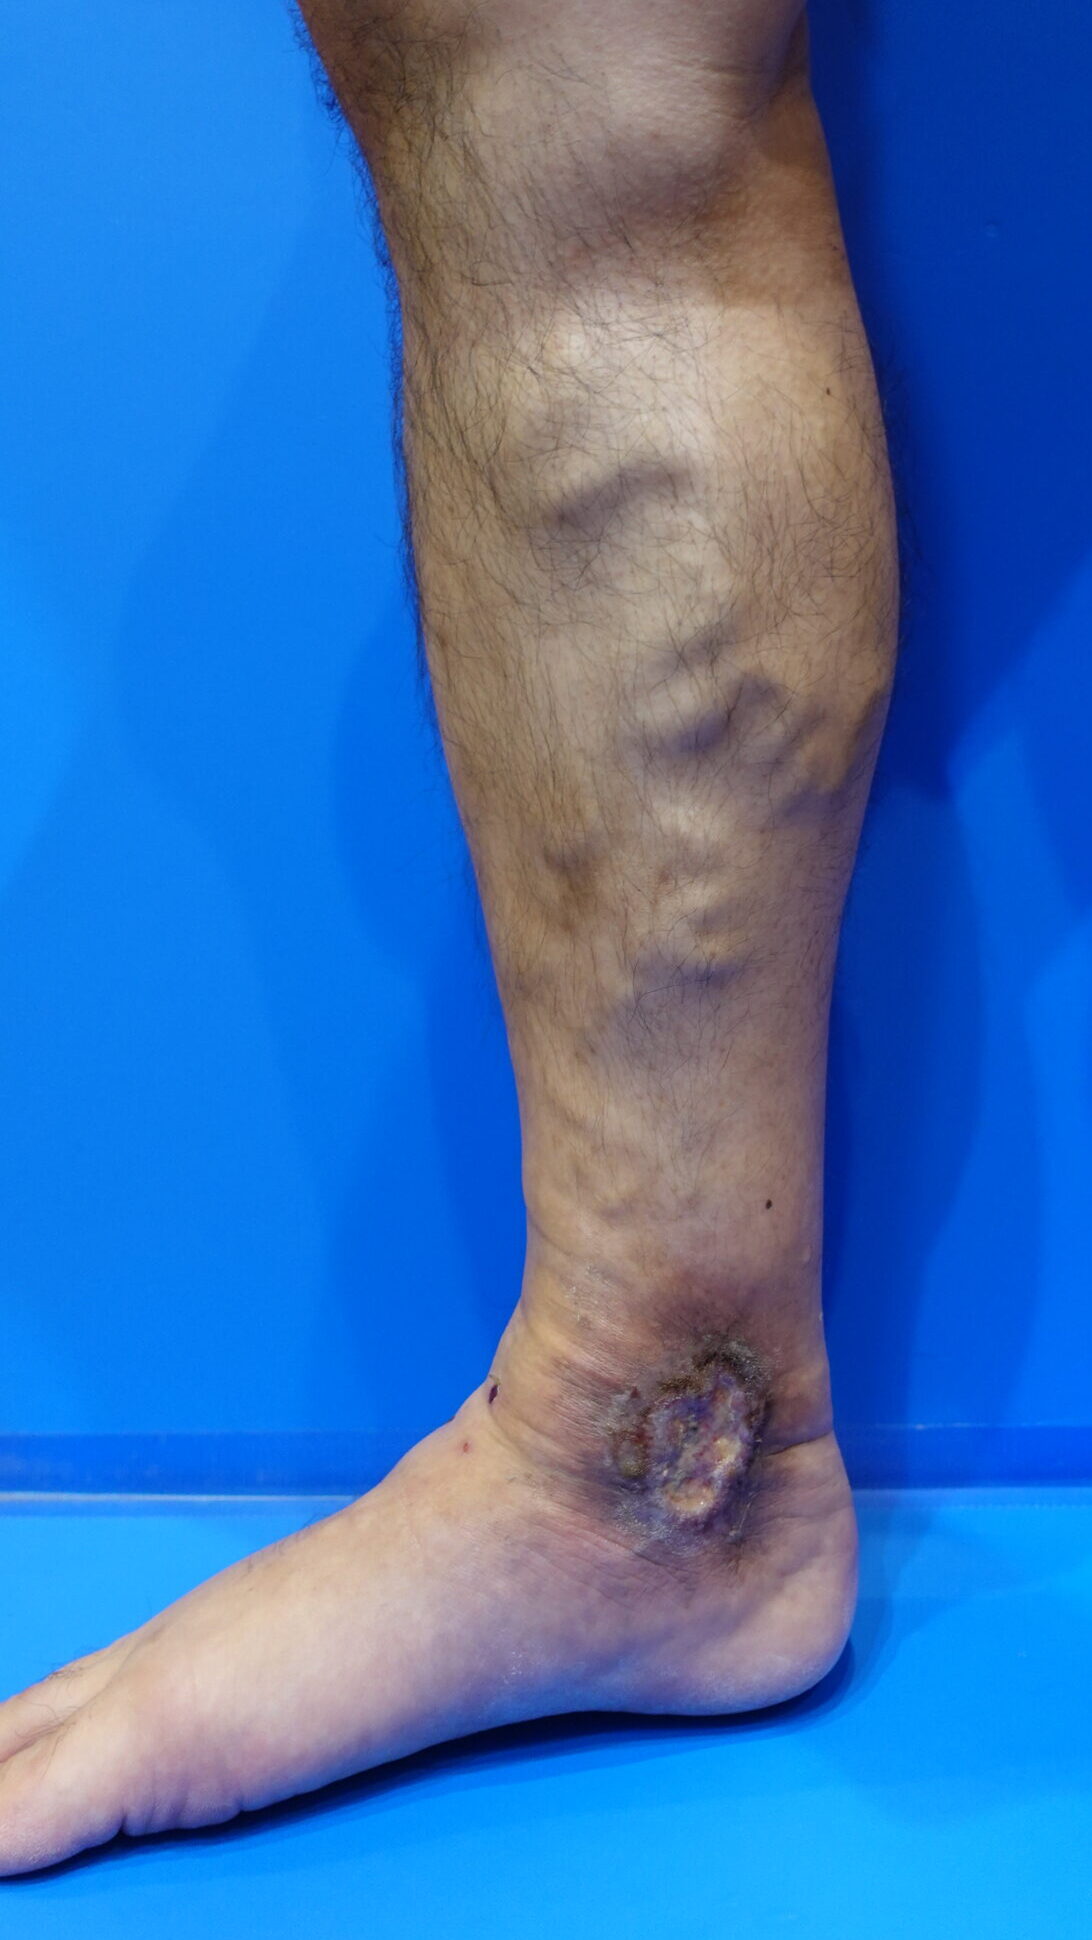

一方で、次のような特徴がそろっている場合、

下肢静脈瘤が原因のうっ滞性皮膚炎が疑われます。

- 足の静脈がボコボコ・クネクネ浮き出ている

- 立つと血管がより目立つ

- 皮膚の黒ずみや湿疹がある

- かゆみが続いている

- 治りにくい傷や皮膚潰瘍がある

下肢静脈瘤 うっ滞性皮膚炎

下肢静脈瘤 皮膚潰瘍